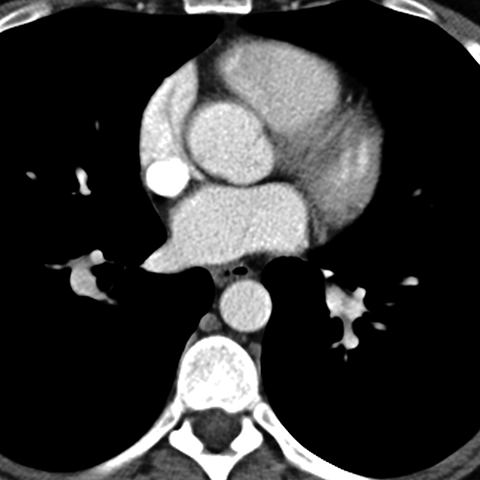

Normal antomy of the aorta (Axial CT) [4 of 5]